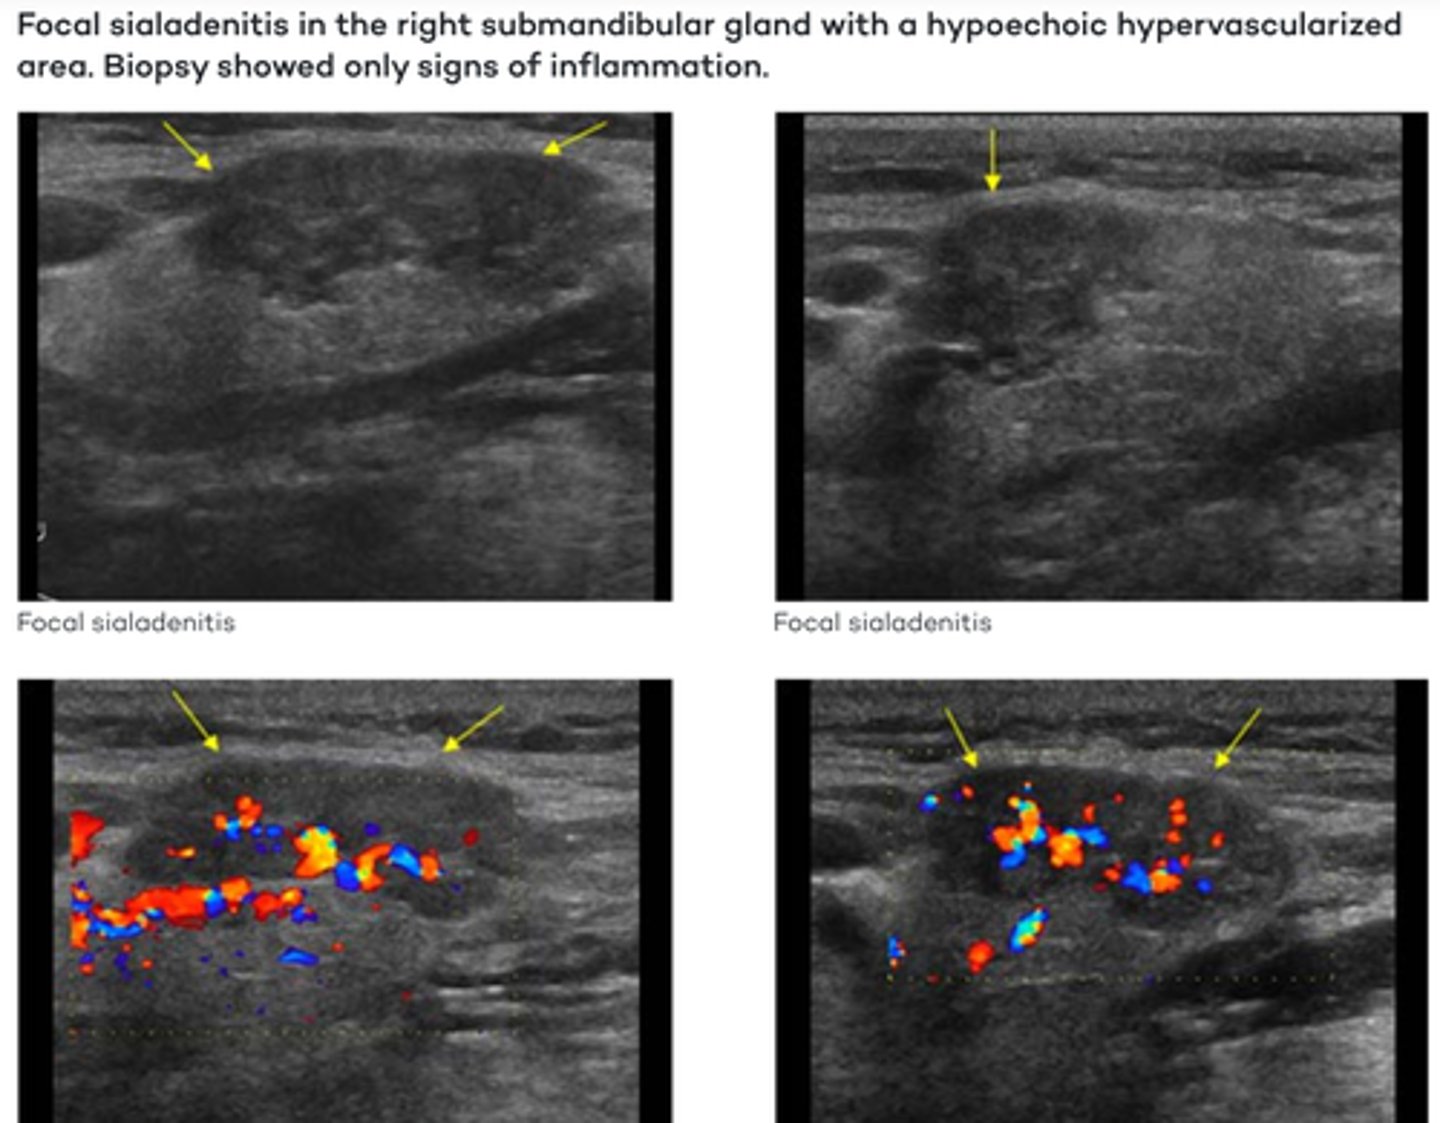

Salivary Gland Pathology - Sialadenitis:

Etiology

-Acute ____ or ____ infection

Clinical findings

-Painful swelling ___laterally

-Swelling during _____

-_____ pain

-_____ of skin

Sonographic findings

-_____, diffusely ____echoic gland

-_____ appearance

-_____vascular

-Cervical _____

-Acute viral or bacterial infection

-Painful swelling bilaterally

-Swelling during eating

-Postprandial pain

-Reddening of skin

-Enlarged, diffusely hypoechoic gland

-Complex appearance

-Hypervascular

-Cervical lymphadenopathy